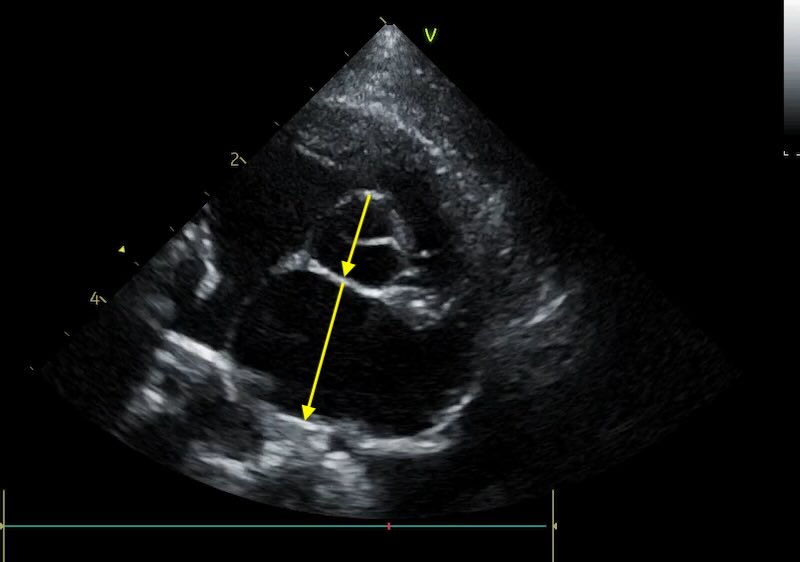

The Moving Target: Through-Plane Motion

The heart is not a static object; it moves cranio-caudally and “bobs” within the chest with every cycle. This root motion (which can be up to 1.5 cm per cycle) creates a specific frustration for the LA:Ao. Remember the ultrasound is slicing the heart transversely, and this means it is moving back and forth through the plane with every heart beat and breath.

The Swedish method requires us to measure the first frame after the aortic valve closes. Paradoxically, this is often the exact moment the heart shifts position, causing the aortic cusps to “vanish” out of frame, or the aorta to appear oval rather than circular.

If the “Mercedes Benz” sign is not visible or looks skewed on that specific frame, your measurement is technically invalid. A common pitfall is to “settle” for a frame that is close enough. If the aorta is elongated, your Ao diameter will be too large, and your ratio will be too low, potentially masking a heart that actually needs medication.

However I also frequently see an aorta that has come out too small, due to being measured too high up the aortic root. Which results in an overestimate of the LA:Ao ratio.